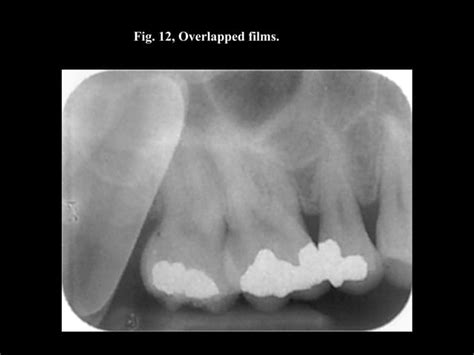

Nathan Mcnicholas Blog